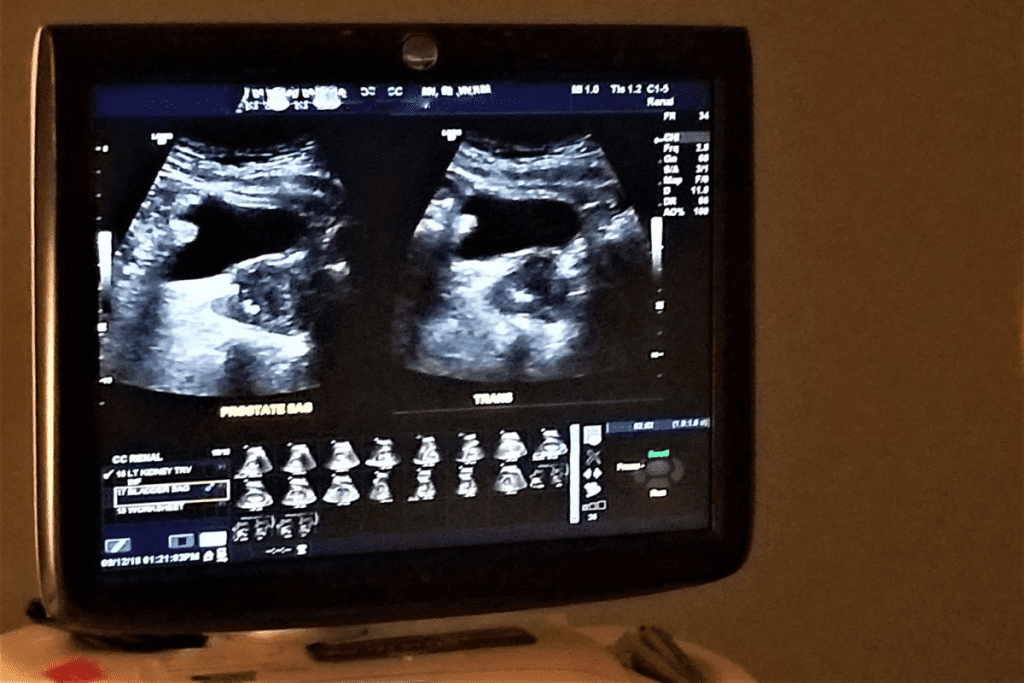

How Ultrasound Imaging Works

Ultrasound uses sound waves to make pictures of inside organs. For kidneys, it checks their size, shape, and where they are.

A transducer sends and gets sound waves. These waves turn into images on a screen. Key parts of ultrasound imaging are:

- Transducer: The device that sends and receives sound waves.

- Sound waves: High-frequency waves that go through the body.

- Image processing: The tech that makes sound waves into pictures.

What Happens During the Examination

During the procedure, the patient lies on an examination table. A clear gel is applied to the abdomen for sound wave transmission. The ultrasound technician uses a transducer to capture images of the kidneys from different angles.

Patients might be asked to hold their breath or change positions. This helps the technician get the necessary images.